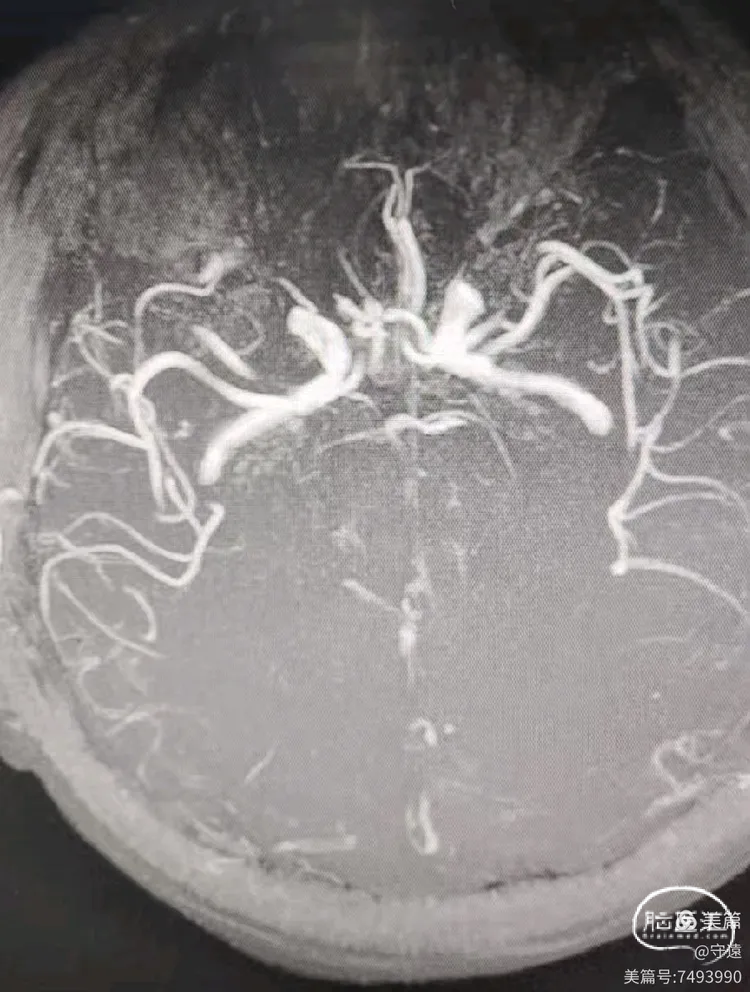

MRA示:双椎动脉、基底动脉中下段未显影。

双侧椎动脉及基底动脉中下段末显影影,左侧后交通向基底供血。